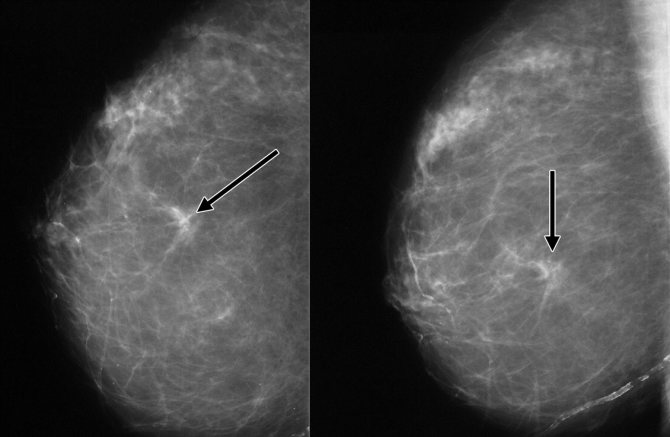

При изучении маммограммы на снимке микрокальцинаты в молочной железе имеют форму чаши, вид сбоку – в форме полумесяца.

Их наличие свидетельствует о злокачественных процессах в молочных железах.

- Плазмоцитарный. На рентгено- или маммографии выглядит в виде пунктиров или червеобразных контуров. Для исключения неинвазивного рака груди врач назначает дополнительное обследование.

- Внутрипротоковый. Это точечно расположенные мелкие кальцинаты в молочной железе, которые на снимке не имеют плотной структуры и по внешнему виду напоминают змеиную кожу. Биопсия тканей поможет исключить или подтвердить наличие рака молочной железы.

Принято считать, что наличие крупных обызвествлений свидетельствует о доброкачественных образованиях и не встречается при раке груди. Чем меньше кальцинаты и чем большее их количество – тем выше вероятность или риск развития рака.